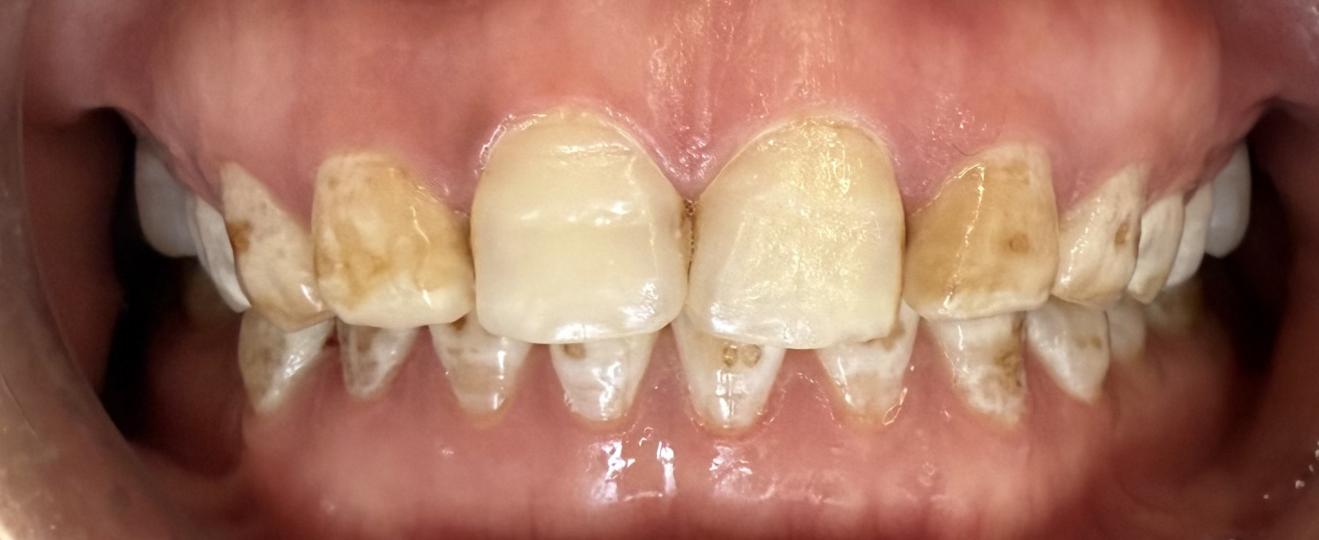

当日,患者前来复诊,戴入最终修复体后,她看着镜中整齐洁白、形态自然的前牙,感觉像换了一副新牙齿!患者表示,咀嚼功能明显改善,公共场合也敢张口大笑了,对医生的精心诊治表示感谢。